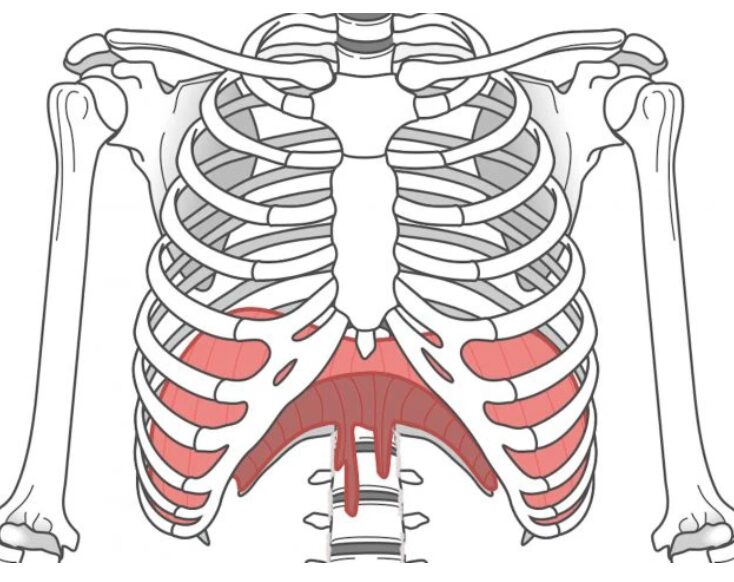

横隔膜って何?どこにあるの?

横隔膜の位置

横隔膜は、肋骨の内側にあるドーム型の大きな筋肉です。胸とお腹を仕切る「仕切り板」のような役割をしています。

イメージしやすく言うと:

- みぞおちの奥にある

- 肺の真下にある

- 肋骨の下縁に沿って広がっている

- パラシュートを逆さにしたような形

横隔膜の付着部位

横隔膜は以下の場所に付着しています:

- 前側:胸骨(胸の真ん中の骨)の裏側

- 横側:肋骨の内側(第7〜12肋骨)

- 後ろ側:腰椎(腰の骨)の前面

ここが重要なポイント! 横隔膜は実は腰椎に直接付着しているのです。具体的には、第1〜3腰椎(腰の一番上から3番目まで)の前面に、「横隔膜脚」と呼ばれる腱のような部分でしっかりとくっついています。